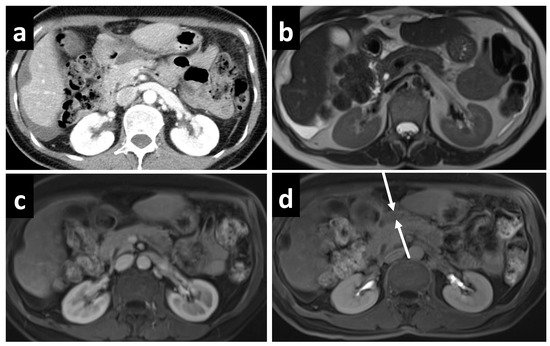

3.3. Evaluation of PCI